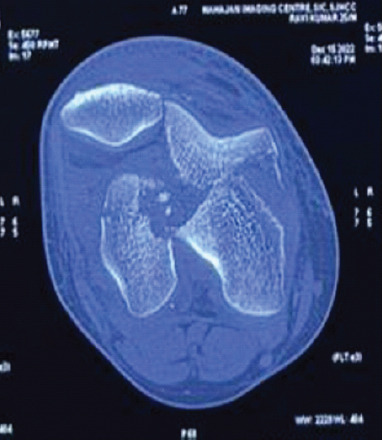

Case report: We present the case of a 25-year-old male who sustained an isolated bicondylar Hoffa fracture following a motorcycle accident. Radiographs and computed tomography (CT) imaging confirmed isolated coronal plane fractures of both femoral condyles (AO 33-B3), without metaphyseal comminution or intercondylar extension. The fracture was managed through a single medial parapatellar approach, using 5 cannulated screws and 2 headless Herbert screws. Post-operative rehabilitation involved early mobilization and progressive weight bearing. At 2 years follow-up, the patient demonstrated excellent functional recovery with a full range of motion (0-140°), no extensor lag, and pain-free full weight-bearing.